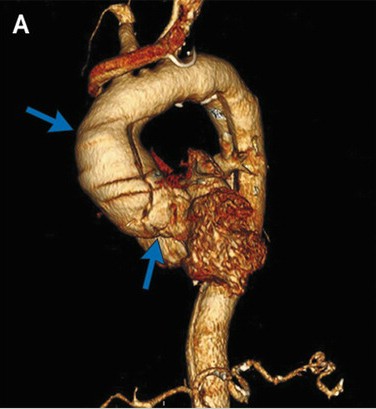

胸腹部CT血管成像示升主动脉瘤(图A,蓝色箭头),DeBakey I型主动脉夹层动脉瘤。该夹层涉及了升主动脉(图B,白色箭头),主动脉弓(图C,蓝色箭头),以及降主动脉(图B、C,红色箭头),结束于肾动脉起点之下。同时还涉及了几条血管分支,包括右头臂动脉、左锁骨下动脉(图C,绿色箭头)和肠系膜上动脉。